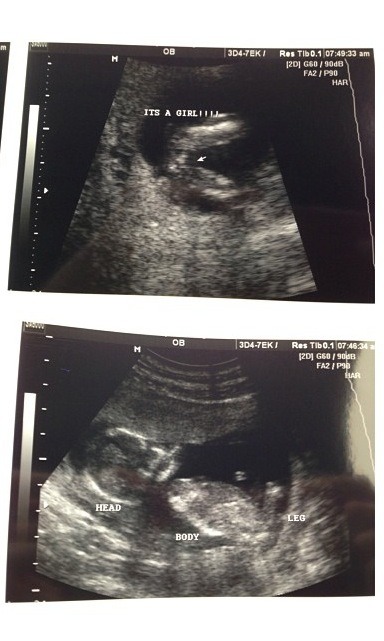

Attachment 12940

This is my girl at 14 weeks if that helps any

Thanks heartmytwo... So you had two dots too... Great to know :) ultrasound tech at 13 weeks said girl, but told me not to paint nursery and tech at 14 weeks 5 days said girl, showed me three lines up close but then said not to get my hopes up till 20 weeks... So frustrating... It's like I know, but don't know lol... Can't tell me family till I'm certain :)

That's a girl! Those are just her swollen girl parts! Congrats!

Yay!!! I praying in two weeks my OB can CONFIRM its all girl... You ladies making me excited now!! I have doubts thinking its the scrotum? But I know all the potty shots of boys at this gestation you can see the PP... Hoping and praying :DD::DD::DD::DD: